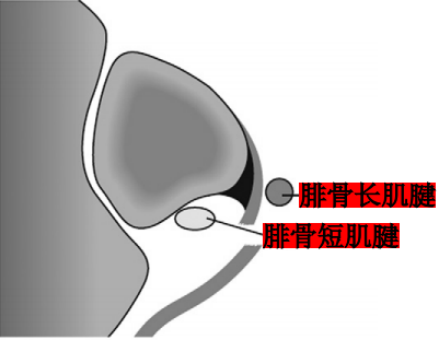

Raikin等学者提出将腓骨沟内腱鞘内半脱位不伴有腓骨上支持带损伤划为腓骨脱位的亚系。这些腱鞘内半脱位共有两型:

A型:腓骨肌腱无撕裂,肌腱暂时换位;

B型:腓骨短肌存在纵向撕裂,腓骨长肌腱自撕裂处半脱位。